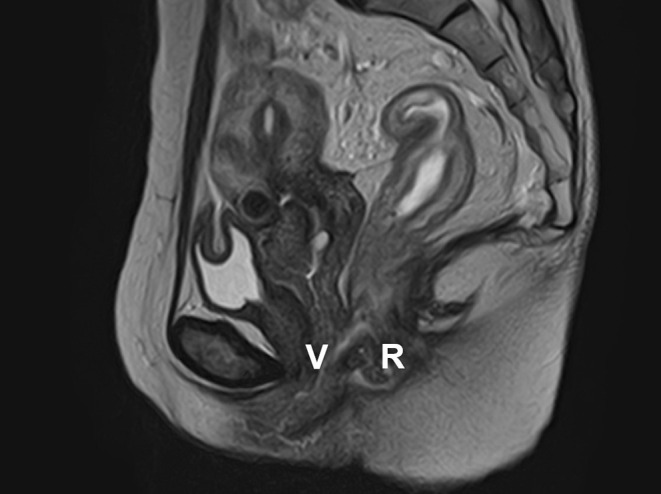

患者是一名 50 岁的日本女性,26 岁时被诊断出患有全结肠炎型溃疡性结肠炎(UC)。她接受了美沙拉嗪和硫唑嘌呤治疗,疾病活动得到了很好的控制。50 岁时,患者出现发热、腹痛、腹泻、血便和肛门疼痛,因此被诊断为 UC 复发。虽然进行了类固醇治疗,症状有所改善,但还是出现了粪便样阴道分泌物,并确诊为直肠阴道瘘(RVF)。患者接受了结肠造口术,并开始使用英夫利西单抗作为 UC 的维持治疗。所有症状均有所改善,在开始使用英夫利昔单抗 6 个月后,确认直肠阴道瘘闭合。迄今为止,她的 UC 一直没有复发。目前只有少数 UC 并发 RVF 的报道,而且这种情况通常很难治疗。据我们所知,此前还没有其他病例在接受结肠造口术和英夫利昔单抗治疗后瘘管闭合的病例;因此,我们对本例病例的报告在文献中具有重要价值。

The patient was a 50-year-old Japanese woman who was diagnosed with total-colitis-type ulcerative colitis (UC) at the age of 26 years. She was treated with mesalazine and azathioprine, and her disease activity was well controlled. At the age of 50 years, the patient was experiencing fever, abdominal pain, diarrhea, bloody stool, and anal pain, which led to a diagnosis of a relapse of UC. Although steroid therapy was administered and tended to improve her symptoms, fecaloid vaginal discharge occurred, and rectovaginal fistula (RVF) was confirmed. Colostomy was performed, and infliximab was initiated as maintenance therapy for UC. All symptoms improved, and RVF closure was confirmed 6 months after the initiation of infliximab. To date, she has been free from relapse of UC. There have been only a few reports of UC complicated by RVF, and this condition is often difficult to treat. To the best of our knowledge, no other case of UC complicated by RVF in which the fistula was closed after treatment with colostomy and infliximab has been previously reported; thus, our report of the present case is valuable to the literature.